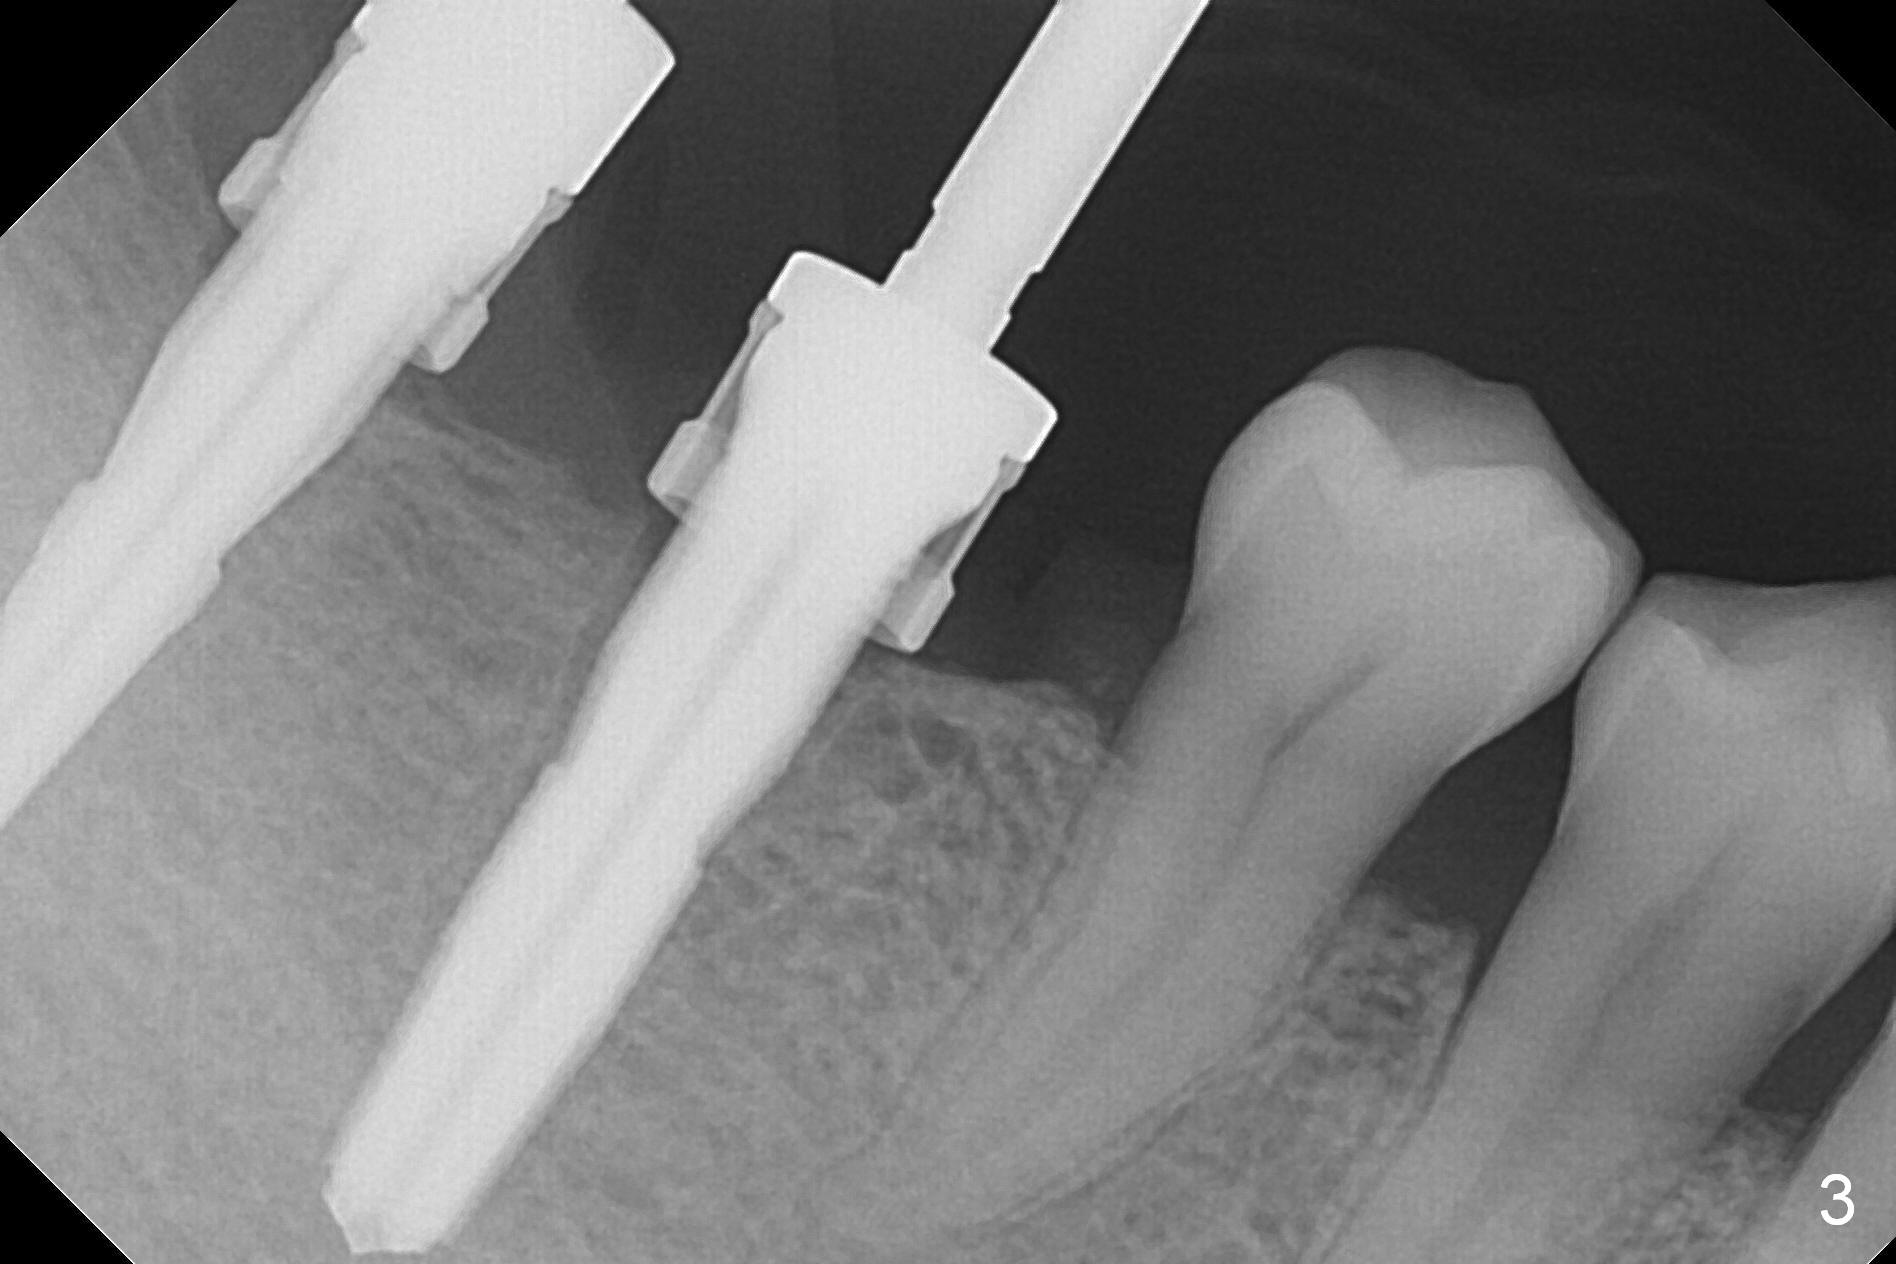

The supraerupted tooth #2 is adjusted using the lower right surgical stent.  Osteotomies are initiated by using starter drill through surgical stent over the ridge (Fig.1) prior to incision.  The initial depths are 10 and 12 mm at the sites of #31 and 30, respectively (Fig.2).  The new sensor with the existing sensor holder cannot reach the deep portion of the lingual vestibule (Fig.2,3).  Without the sensor holder, the #2 sensor with rounded corners has no problem showing the Inferior Alveolar Canal (Fig.4 red dashed line).  The two implants (5x12 and 5x14 mm, Fig.5) are placed with >50 Ncm.  Cemented abutments are immediately placed (6.8x4(2) and 6.8x4(3) mm) to reduce suture tension (after autogenous bone graft and collagen dressing) and hold periodontal dressing in place.  The wound does not heal completely 15 days postop (Fig.6).  The patient reveals that he smokes 1/2 pack per day.  There is crestal bone resorption 4 months postop (Fig.7 *).  It appears that for smokers, implants should be smaller, placed deeper and buried.  In addition, his oral hygiene is not good.